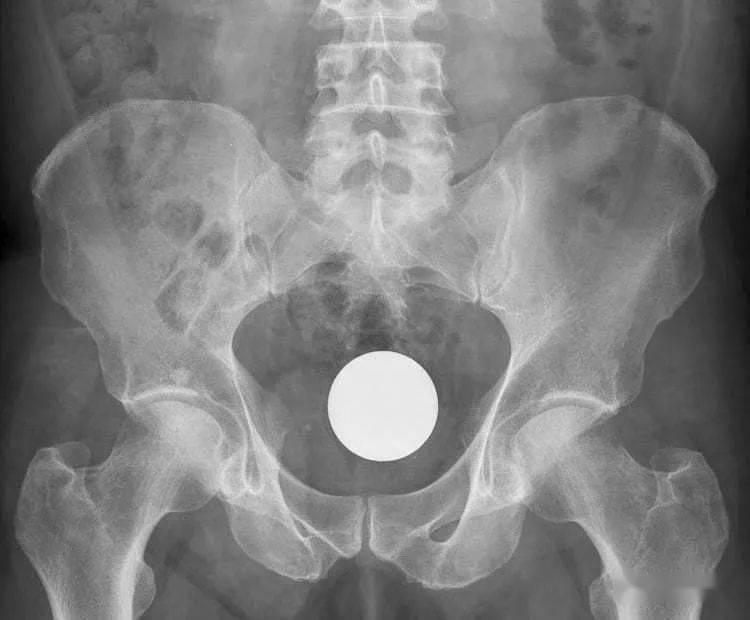

▷台球警告:晚上裸体打台球 , 可能会导致严重伤害 。